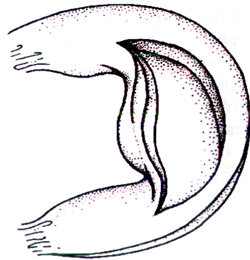

Типовий розрив меніска з вивихом типу «ручка лійки» на схемі і через артроскоп